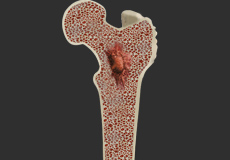

Osteomyelitis

Bone infection or osteomyelitis is a serious medical condition that needs immediate medical attention. Infection may occur due to an open fracture or surgery or infection in one area of the body may spread to the bone via the bloodstream.